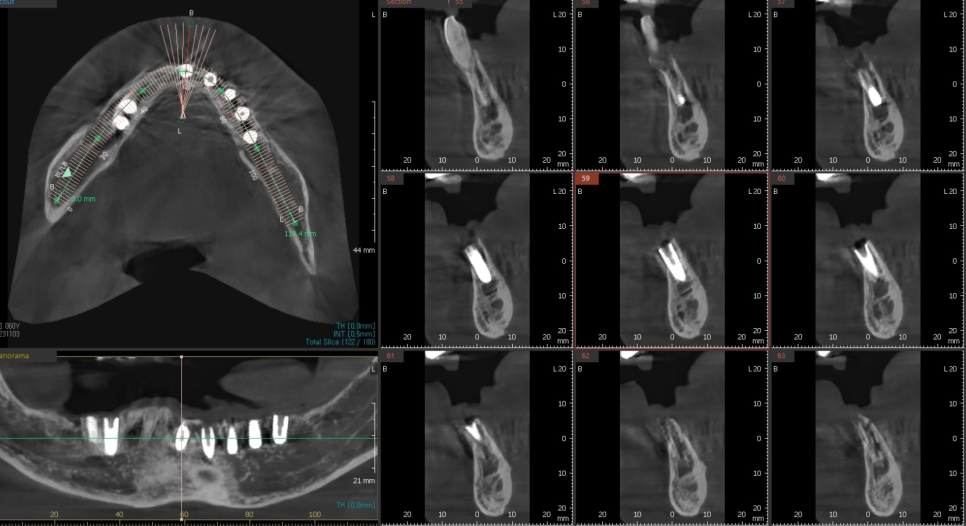

저희는 디지털 시스템을 활용하여

3D 데이터를 통해 신경의 위치를 미리 파악하고,

잇몸뼈가 가장 튼튼한 곳을 골라

최적의 각도로 설계를 마쳤습니다.

수술 과정

미리 만든 가이드를

입안에 고정하고 수술을 진행하니,

계획했던 위치와 깊이에 맞춰 임플란트 7개가

안정적으로 자리를 잡았습니다.

231103

심어야 할 개수가 많고 잇몸뼈 상태도

좋지 않은 어려운 조건이었지만,

가이드 덕분에 이미 정해진 위치에

오차 없이 신속하게 마무리할 수 있었습니다.